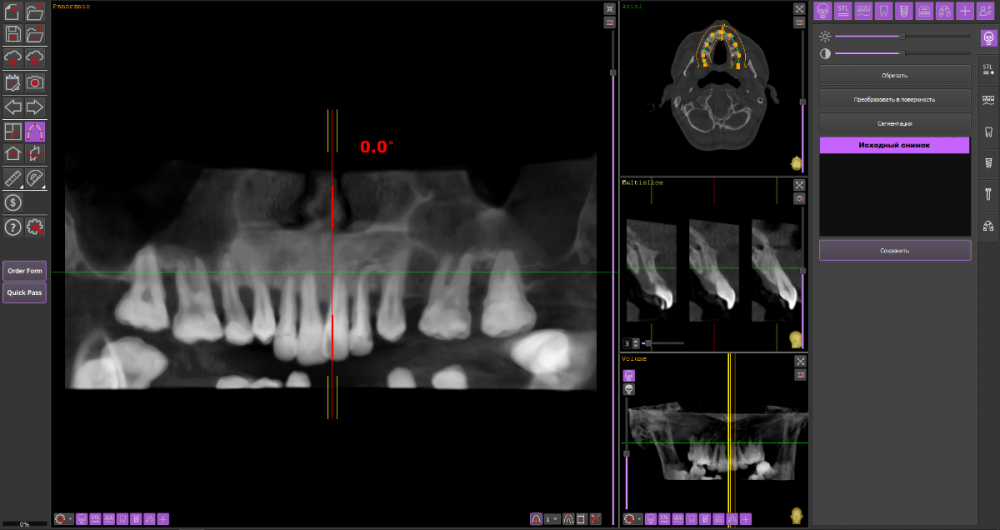

Сергей34 Опубликовано 19 октября, 2022 Поделиться Опубликовано 19 октября, 2022 Приветствую господа и дамы. Значит картина следующая, мне 34 года и обладаю пародонтитом. Нижних зубов уже почти лишился осталось по краям 6 зубов которые прилично шатаются. (несколько месяцев ношу протез квадротти частичный). Верхние зубы 12 шт пока стоят (их буду шинировать, кюретаж все дела), этих манипулаций хватит ещё года на 2-5 может - как повезёт. На верхней челюсти по кости всё очень печально, на верху по бокам без синус лифтинга вообще не поставить импланты. (а синус лифтинг и основательную неопределенность результата я не вывезу по финансам и здоровью). Принял решение ставить вниз импланты, есть возможность поставить 4 или 6 имплантов. А в перспективе через 3-5 лет уже когда верхние зубы начнут выпадать поставить на верх 4 импланта что получится поставить. ------------------- Так вот в чём мой вопрос, какую конструкцию будет правильнее поставить сейчас внизу на 4/6 имплантов, чтобы в будущем когда буду протезировать верх эти 2 материала друг друга не разбили. Врач мне сказал что наверху без синус лифтинга можно сделать только сьёмный протез на 4 имплантах. Подскажите пожалуйста какое протезирование сейчас будет оптимально выбрать на низ и как это выглядит, если не сложно приложите пожалуйста фото этого решения. Спасибо. Ссылка на комментарий

Сергей34 Опубликовано 9 ноября, 2022 Автор Поделиться Опубликовано 9 ноября, 2022 (изменено) 24.10.2022 в 21:48, Bier сказал: я бы ставил 6/6 условия позволяют. Ждать особого смысла нет. По верху подскажите пожалуйста, я решился удалять верх тоже. Есть ли возможность установить 4 импланта и несьёмную конструкцию на них, имеет ли смысл в долгосрочной перспективе? Или без синуса никак Изменено 9 ноября, 2022 пользователем Сергей34 Ссылка на комментарий

Bier Опубликовано 9 ноября, 2022 Поделиться Опубликовано 9 ноября, 2022 1 час назад, Сергей34 сказал: По верху подскажите пожалуйста, я решился удалять верх тоже. Есть ли возможность установить 4 импланта и несьёмную конструкцию на них, имеет ли смысл в долгосрочной перспективе? Или без синуса никак да, можно 1 Ссылка на комментарий